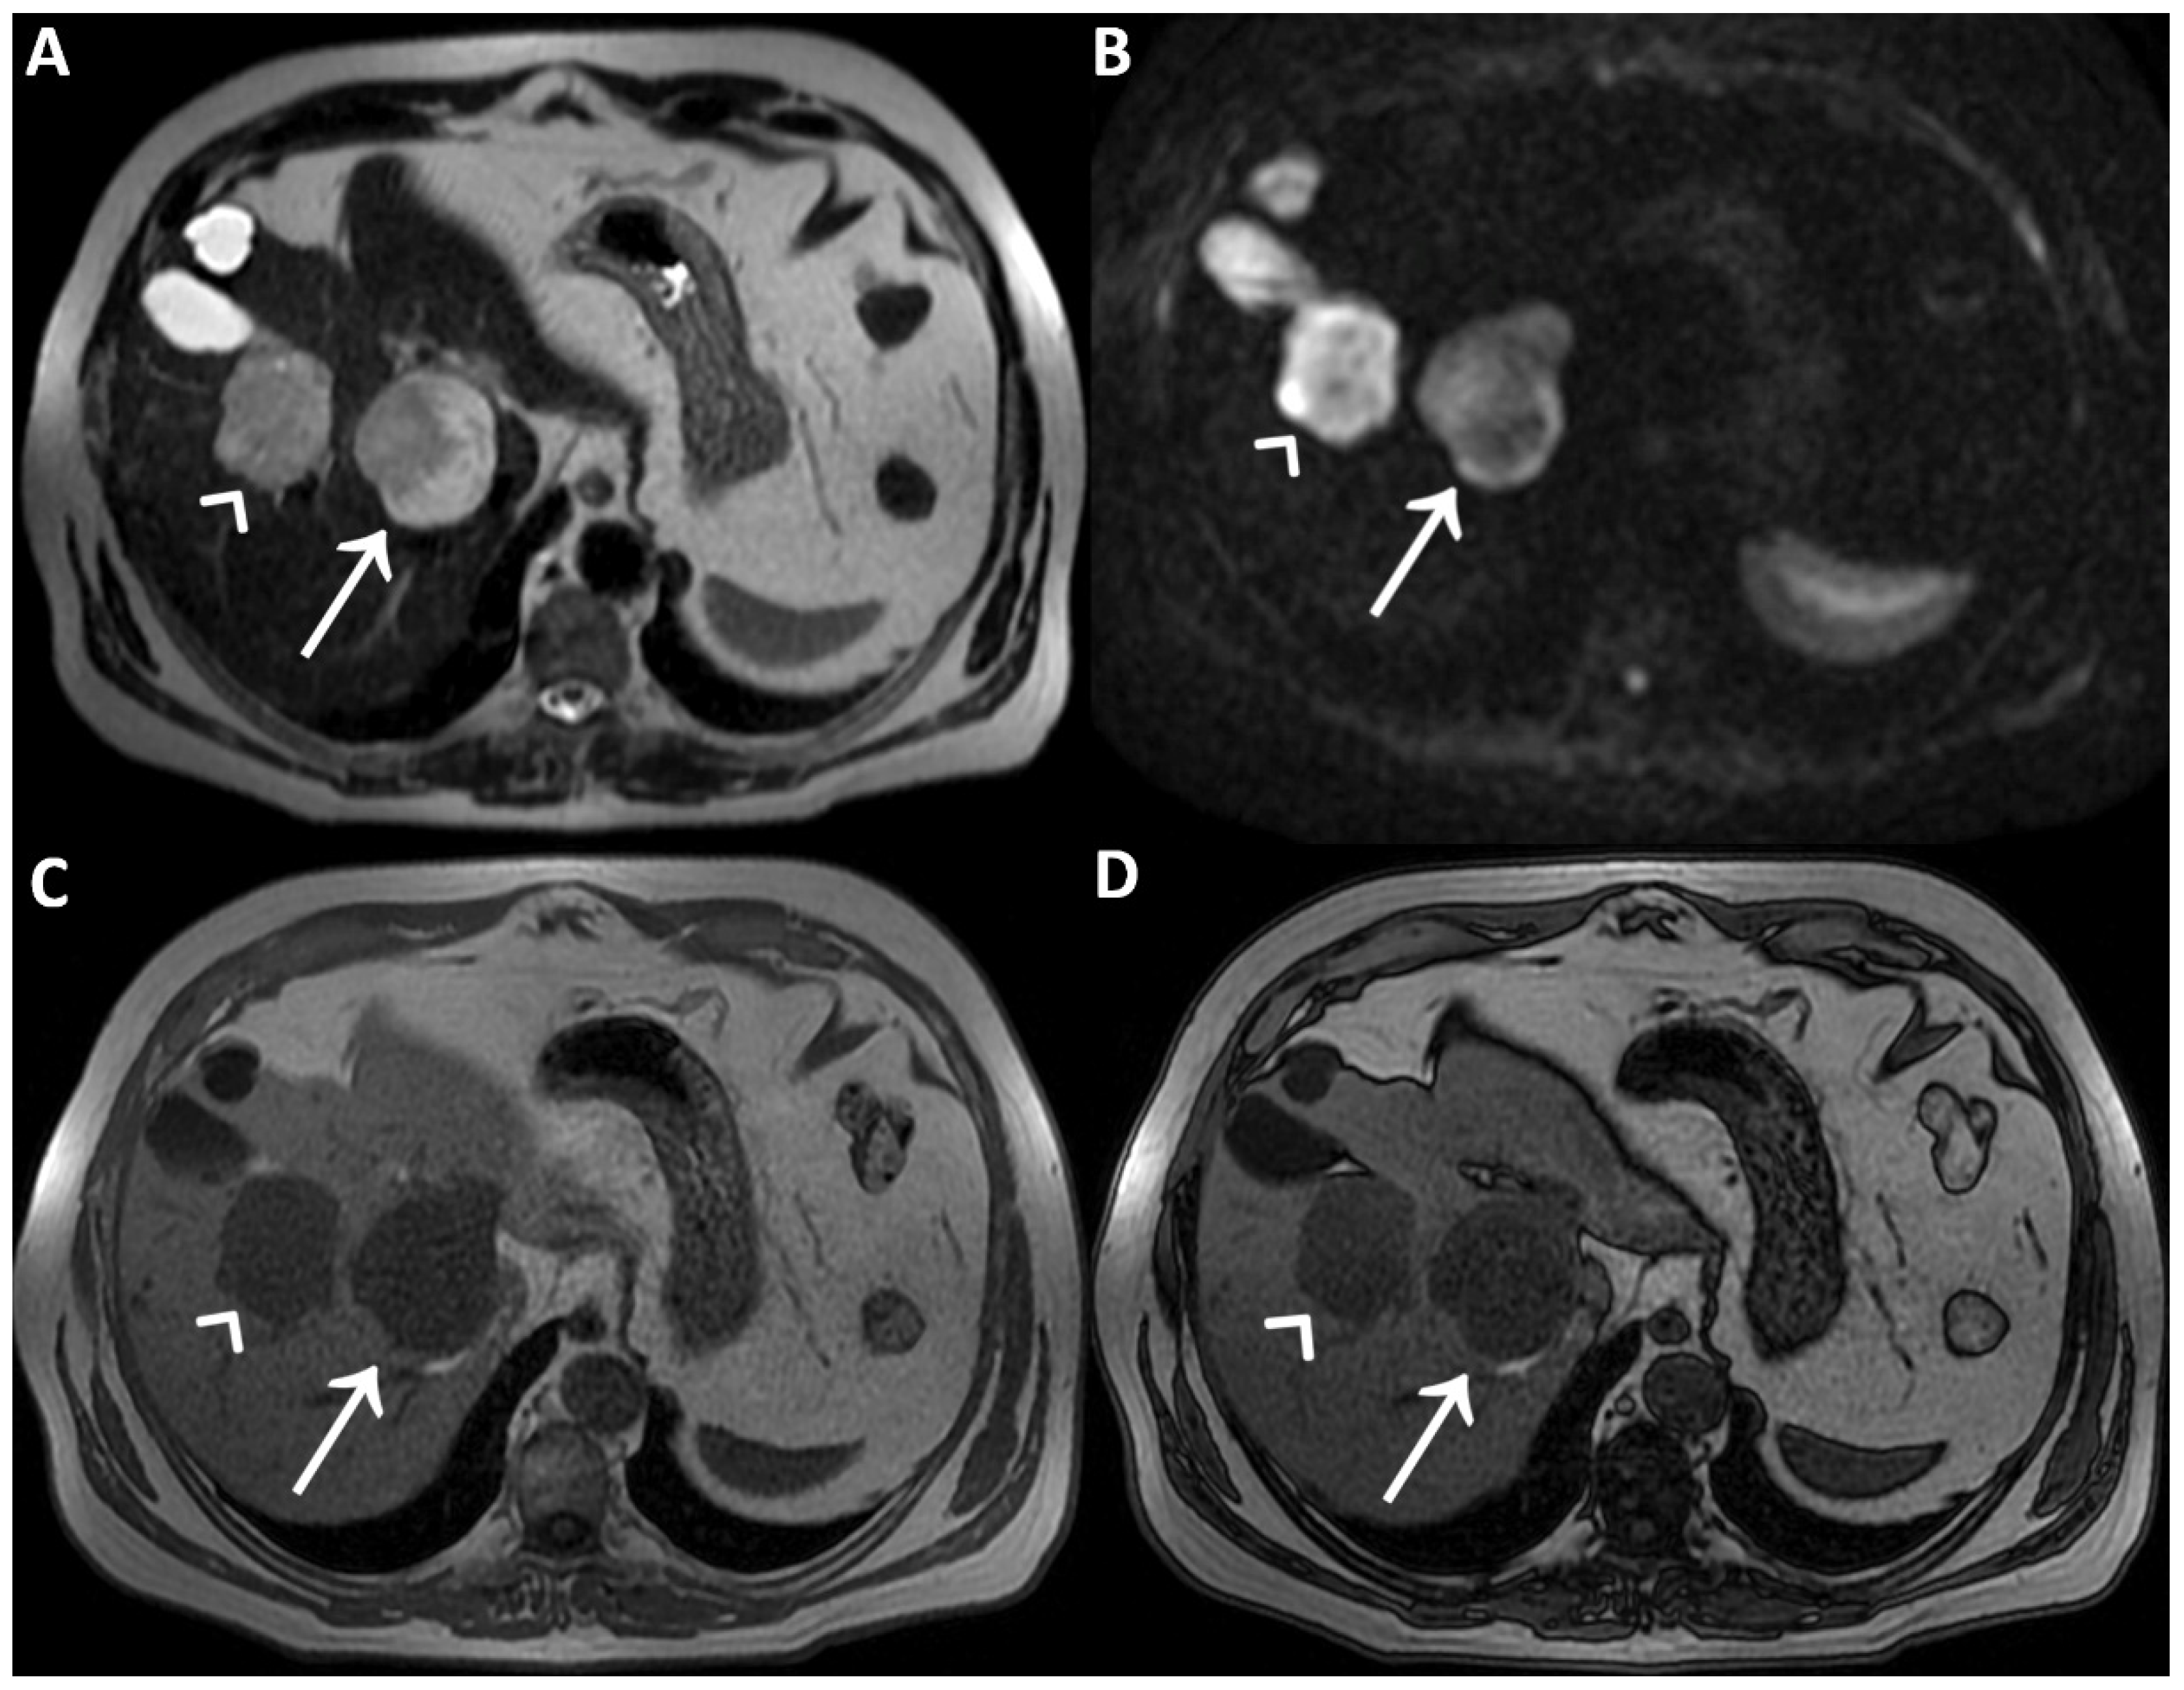

A man in his early 60s with unremarkable medical history and normal laboratory data underwent an abdominal ultrasound for insurance reasons, which detected two liver lesions, the largest one localized deeply in the hepatic parenchyma. Due to the patient’s high body mass index, which reduced the ultrasound’s diagnostic quality, panoramic imaging was required to achieve the final diagnosis. Therefore, the patient underwent liver Magnetic Resonance Imaging (MRI) performed with hepatospecific contrast agent (Gd-EOB-DTPA). MRI was performed by using a 1.5 T superconducting system (Signa; GE Medical Systems, Milwaukee, Brookfield, WI, USA) with a body phased-array multicoil for signal detection. The two liver lesions appeared to be inhomogeneously hyperintense on T2-Weighted Images (T2WI) (straight arrow and arrowhead in (A)) and on Diffusion-Weighted Images with b-value = 800 (DWI) (straight arrow and arrowhead in (B)) and homogeneously hypointense on T1-Weighted Images (T1WI) (straight arrow and arrowhead in (C), in-phase T1WI, and (D) opposed-phase T1WI). It was not possible to establish the benignity of the two liver lesions evaluating T2WI and DWI acquired after contrast agent administration, in particular due to the inhomogeneous signal intensity shown on T2WI. To ascertain that it had not been caused by the contrast-induced reduction in the hydrogen nuclei relaxation time, it was necessary to re-acquire the same images without previous contrast administration a few days later.